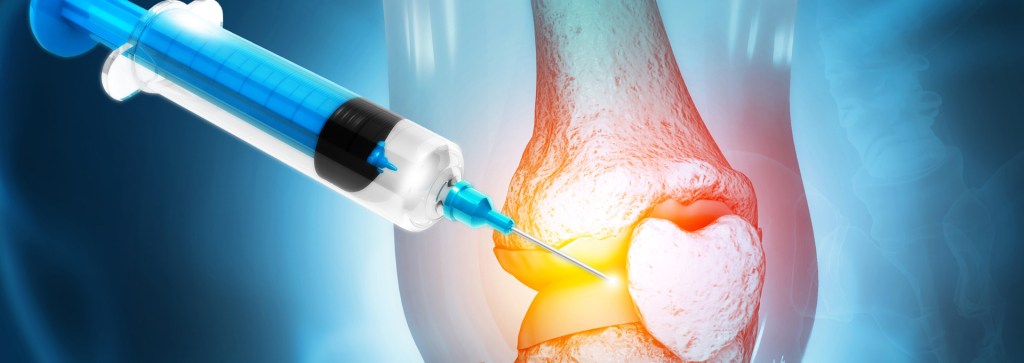

Arthrosamid presents a fresh approach to treating knee osteoarthritis, providing patients with a viable option to existing therapies. The treatment employs an inventive non-biodegradable hydrogel technology composed of 97.5% water and 2.5% cross-linked polyacrylamide backbone. Upon injection into the knee joint, Arthrosamid acts as a cushion, assuaging pain and delivering secure and long-lasting relief in a single shot.

Arthrosamid is a type of injection known as an intra-articular polyacrylamide hydrogel (iPAAG) used to alleviate the symptoms of knee osteoarthritis. It works by replenishing the synovial fluid’s thickness, enhancing joint lubrication, and cushioning. Additionally, it creates a cushioning effect by integrating into the synovium of the inner joint capsule.

Arthrosamid acts to cushion the joint, resulting in a reduction in pain, stiffness, and improved movement. The hydrogel is non-degradable, providing long-lasting relief, which can enhance your quality of life. According to clinical trials, patients experienced a considerable reduction in pain symptoms by the fourth week after their injection. Unlike other injectable treatments, this reduction was sustained at the two-year follow-up period.

Arthrosamid is administered through a single injection, under ultrasound, into the knee’s intra-articular cavity by a qualified specialist. Prior to the injection, a local anaesthetic is given to numb the area around the knee, which may cause a slight stinging sensation. Unlike surgery, the injection is a minimally invasive procedure that can be done on an outpatient basis. Before the injection, antibiotics are provided to prevent any potential injection risk.